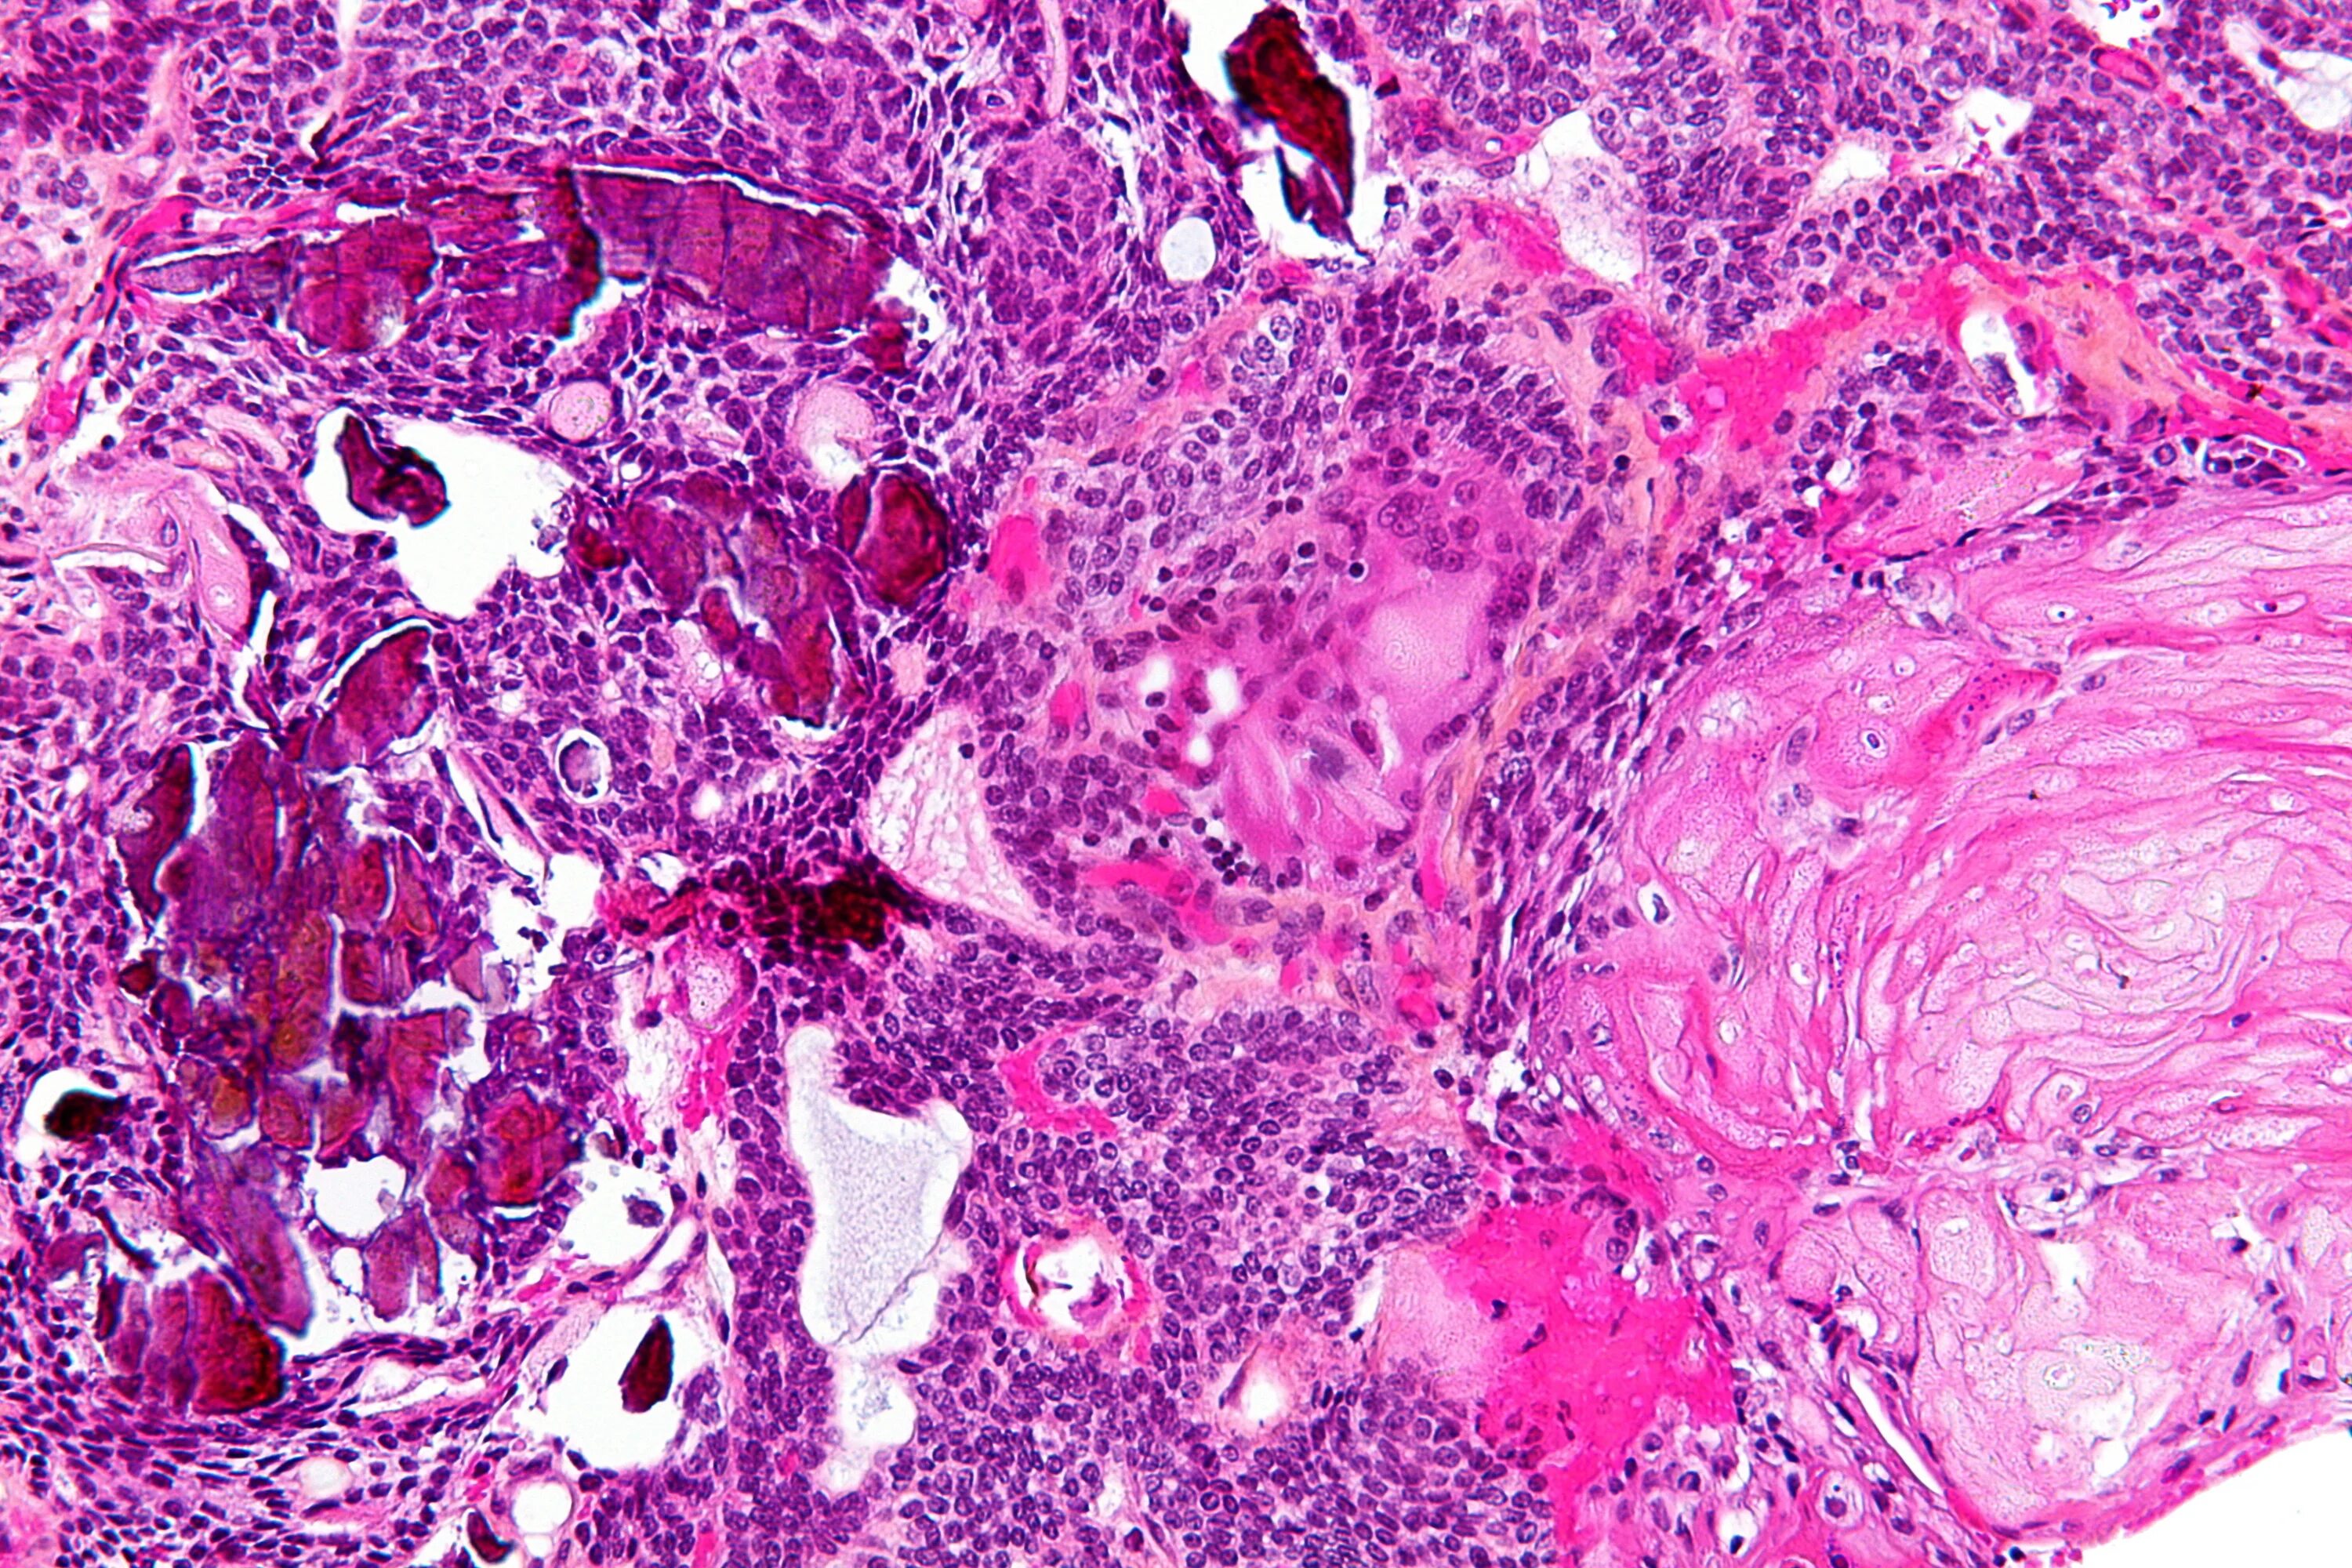

Гистология головного мозга